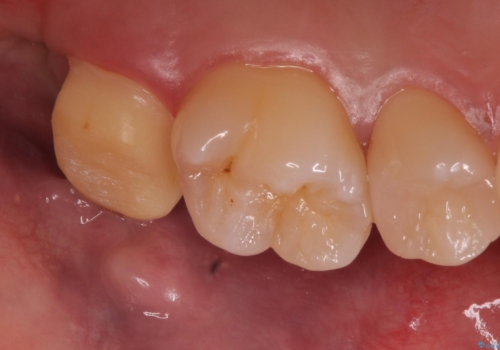

歯ぐきの形を整え、外れにくい被せ物を装着

歯のみでなく歯茎の調整も行うことで、外れにくい被せ物を装着することが可能になります。